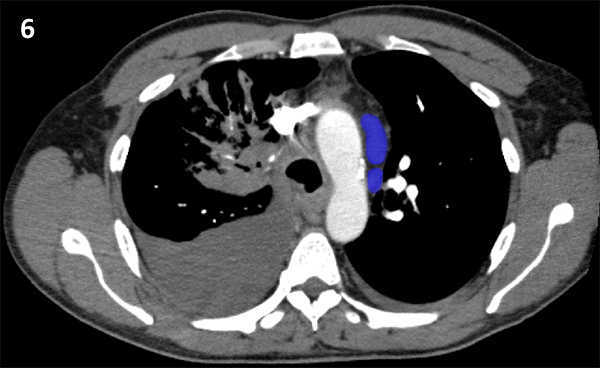

Nodal zones and stations according to the International Association for the Study of Lung Cancer (IASLC) node map.

Table (above): Nodal zones and stations according to the International Association for the Study of Lung Cancer (IASLC) node map. (Source: 1,2) *Depends on the side of the tumour.